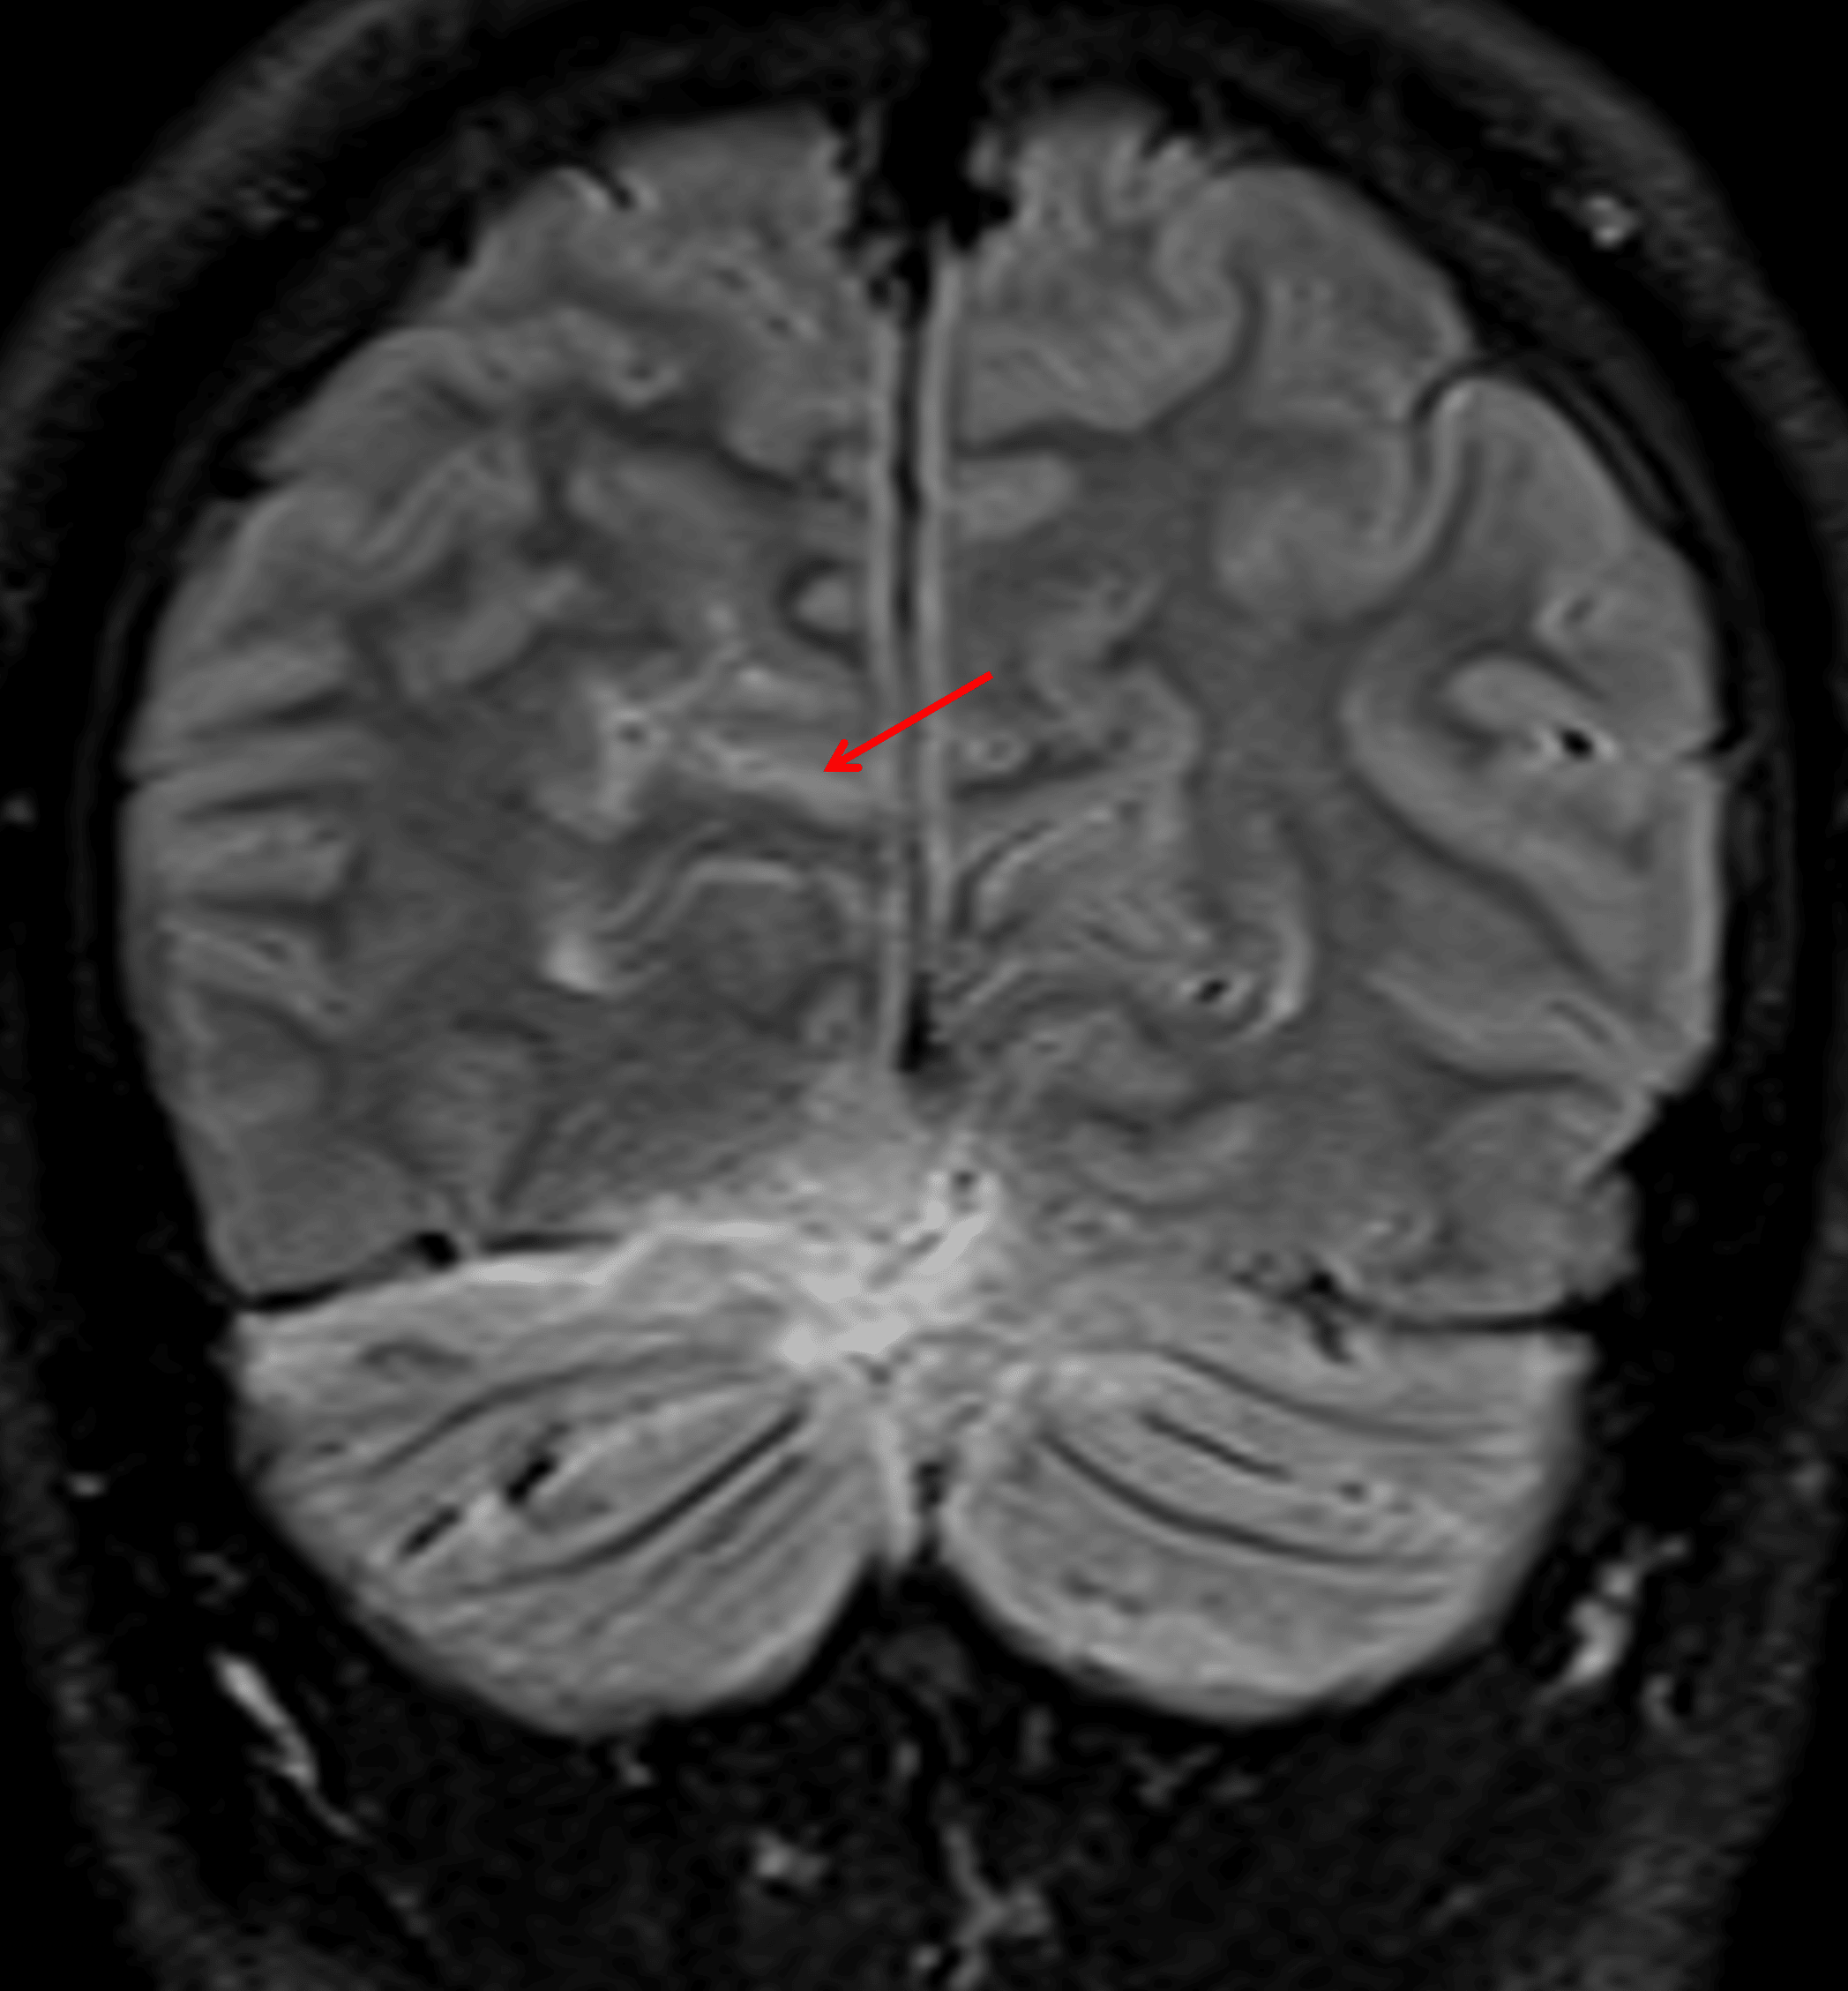

FLAIR signal hyperintensity in a right occipital sulcus (red arrow), which may also relate to leptomeningeal tumor dissemination.